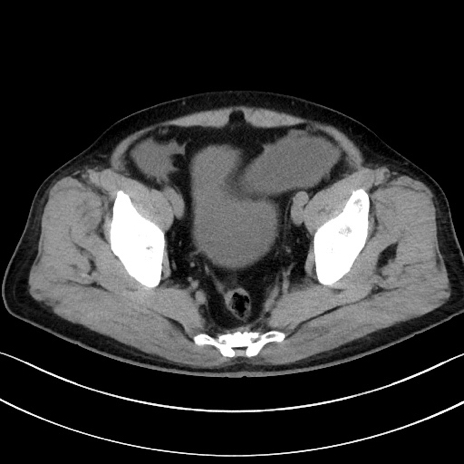

冠状断像

症例15(横断像)

【症例】70歳代男性

【主訴】腹痛

【現病歴】今朝から腹痛あり。全体的に痛い。特に左上の方。排ガスが今日はない。冷や汗が出る。

【既往歴】直腸癌術後

【身体所見】左側腹部〜上腹部に圧痛あり。腹膜刺激症状明らかなではない。軽度反跳痛。左下腹部に術後瘢痕あり。

【データ】WBC 7700、CRP 0.02